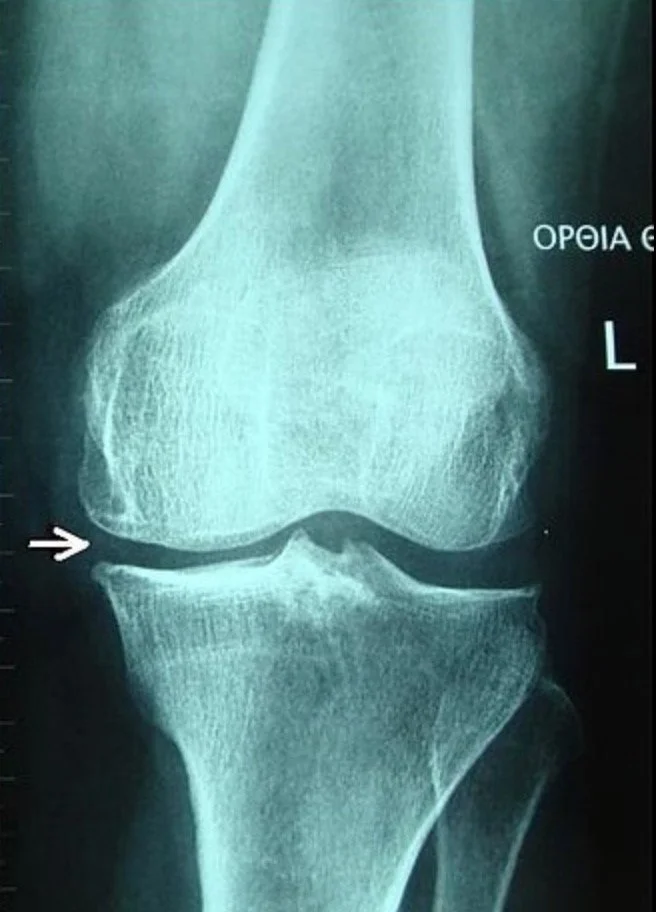

Image Courtesy of Physiopedia

Knee osteoarthritis is one of the most common diagnoses encountered in orthopaedic practice.  Multiple treatment options are available including physical therapy, bracing, corticosteroid injections, hyaluronic acid (gel) injections, platelet-rich plasma (PRP) injections, and surgery (total knee replacement).